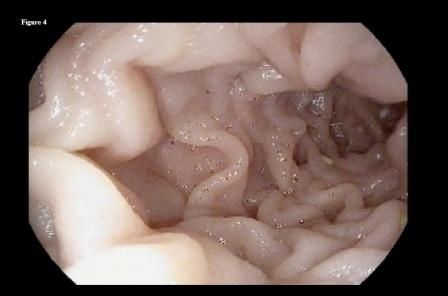

Laboratory tests revealed the following: hemoglobin 11 g/dL (12-16 g/dL); hematocrit 34% (37%-47%); MCV 82 fL (80.4-95.9 fL); MCH 26 pg/cell (27-31 pg/cell); MCHC 30.2 g/dL (32-36 g/dL); and RDW 14.6% (12%-15%). There were no electrolyte abnormalities, including hypokalemia and a hypochloremic metabolic alkalosis. Abdomen and pelvis CT with contrast revealed that the patient was status post partial gastrectomy. It also showed chronic stable intrahepatic and extrahepatic biliary ductal dilatation and pancreatic duct dilatation with pancreatic atrophy. Upper endoscopy was performed in view of the patient’s history of refractory PUD and multiple abdominal surgeries. It showed a normal gastric remnant, an ulcer at the anastomotic site, and a large bezoar on the gastric side of anastomosis (Figures 1 and 2). Biopsy from the mass showed vegetable fibers, confirming the diagnosis of phytobezoar.

She followed this regimen for the following 3 months with significant improvement in her symptoms. A repeated upper endoscopy performed at 3 months after presentation showed complete dissolution of the phytobezoar, with a clear view of the distal end of the gastric remnant (Figure 3) and the jejunal side of the anastomosis (Figure 4).